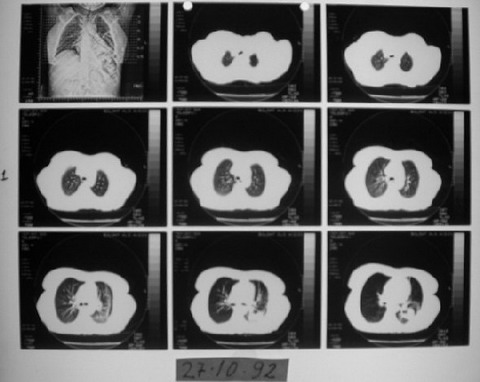

1991 yılında az diferansiye fibröz malign mezotelioma teşhisi konulan 53 yaşındaki kadın hasta, çok düşkün haldeyken immünomodülatör tedavi ile 9 ayda tam iyileşme sağladı. 2000 yılında hasta remisyondaydı ve 9 yıl boyunca hastalık belirtisi göstermedi.

Ödem kayboldu, radyoloji normale yakın

Radyolojik bulgular normale yakın hale gelmişti ve immünomodülatör tedaviyi kesmesi önerildi.